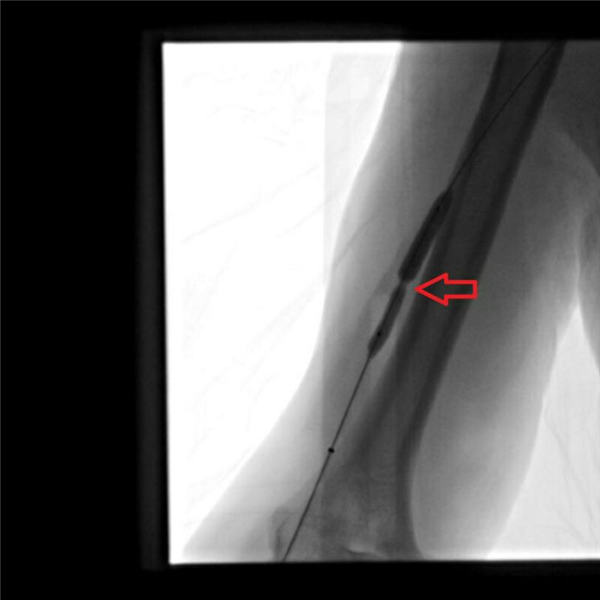

随后,两位主任通力协作,通过放置球囊扩张的方法,对血管的三处狭窄段分别用球囊扩张后,可见狭窄段部分或者完全扩张(下图红色箭头所示)。